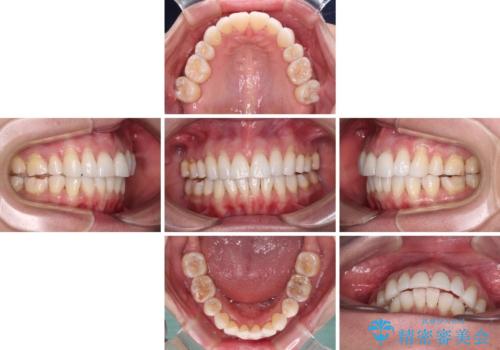

- 上の前歯の出っ歯を治したいとのことで来院された患者様です。

後戻りによる再矯正というもともあり、インビザラインを希望されていました。

上顎の歯は後方移動とIPR(歯と歯の間を削る)によって口元が引っ込むように、下顎は歯列全体の拡大とIPRによって上顎とバランスよく咬み合うように設計し、インビザラインにより治療を行うこととしました。

治療を開始して暫くして、勤務先から2年以上帰国することができず、それまでの移動がほとんど後戻りしてしまい、帰国後に再度後戻りをリカバリーするための治療を行うこととなりました。

5年以上の治療期間がかかりましたが、気になっている部分を改善することができました。